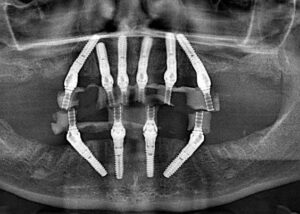

Sistemul Sky Fast & Fix, dezvoltat de liderul german Bredent, este o metodă de implantologie avansată care permite refacerea întregii danturi (pe una sau ambele arcade) folosind un număr redus de implanturi.

Fără adiție de os: Datorită angulării implanturilor posterioare, se folosește osul nativ existent, evitând adesea intervențiile complexe de sinus lift.

Dr. Carmen Popa deține o vastă experiență în reabilitările complexe pe implanturi. Fiecare caz este planificat digital, utilizând tehnologie de ultimă oră pentru a asigura o poziționare ideală a implanturilor Sky Fast & Fix.

Sky Fast & FixConsultația și Diagnosticul: Evaluarea stării de sănătate orală prin radiografii și scanări 3D.

Intervenția Chirurgicală: Îndepărtarea dinților compromiși și inserarea a 4/6 implanturi la mandibulă sau maxilar.